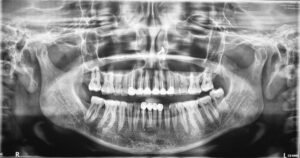

With “CARESTREAM CS-9600” the OPG image quality is one of the finest where almost all details of anatomical region, in any age group can be interpreted to perfection.

PANORAMIC IMAGES IN DIFFERENT AGE GROUPS 👇🏻